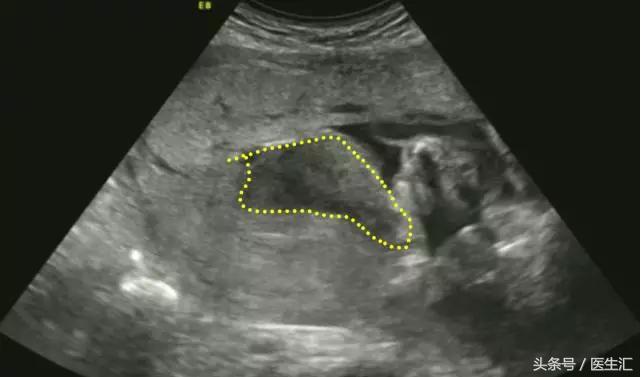

1.胎盘内血池或血窦:位于胎盘实质内,在胎盘切面内呈不规则液性暗区,内有云雾状回声呈沸水征。(见图2黄色圈内)

图2,胎盘左侧缘及右侧缘后方与宫壁间均见条状无回声区,范围约:40mm×14mm(左侧缘),36mm×9mm(右侧缘),内见密集光点浮动,似可探及静脉血流信号。